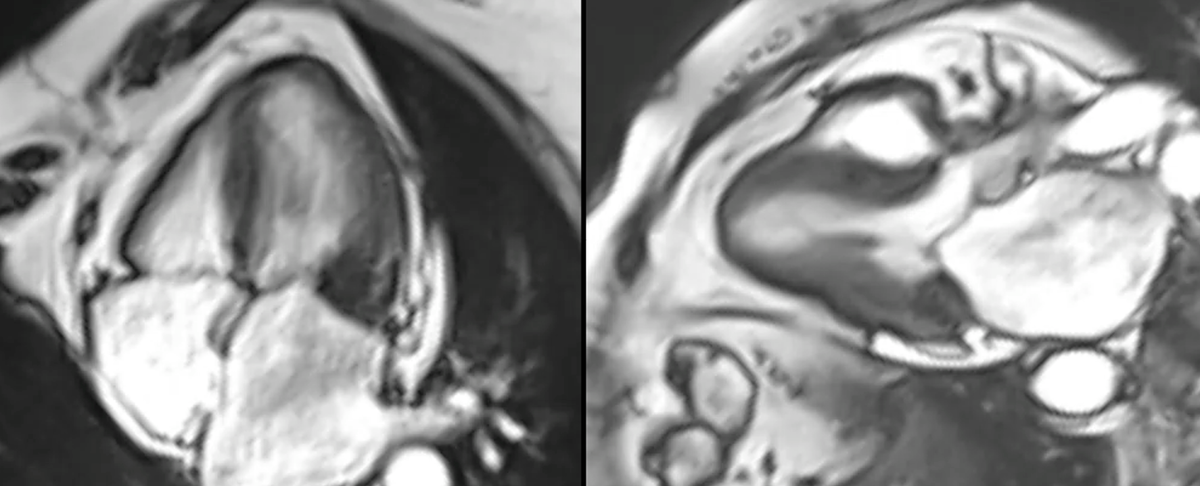

Mass or pseudomass?

This post is for subscribers only